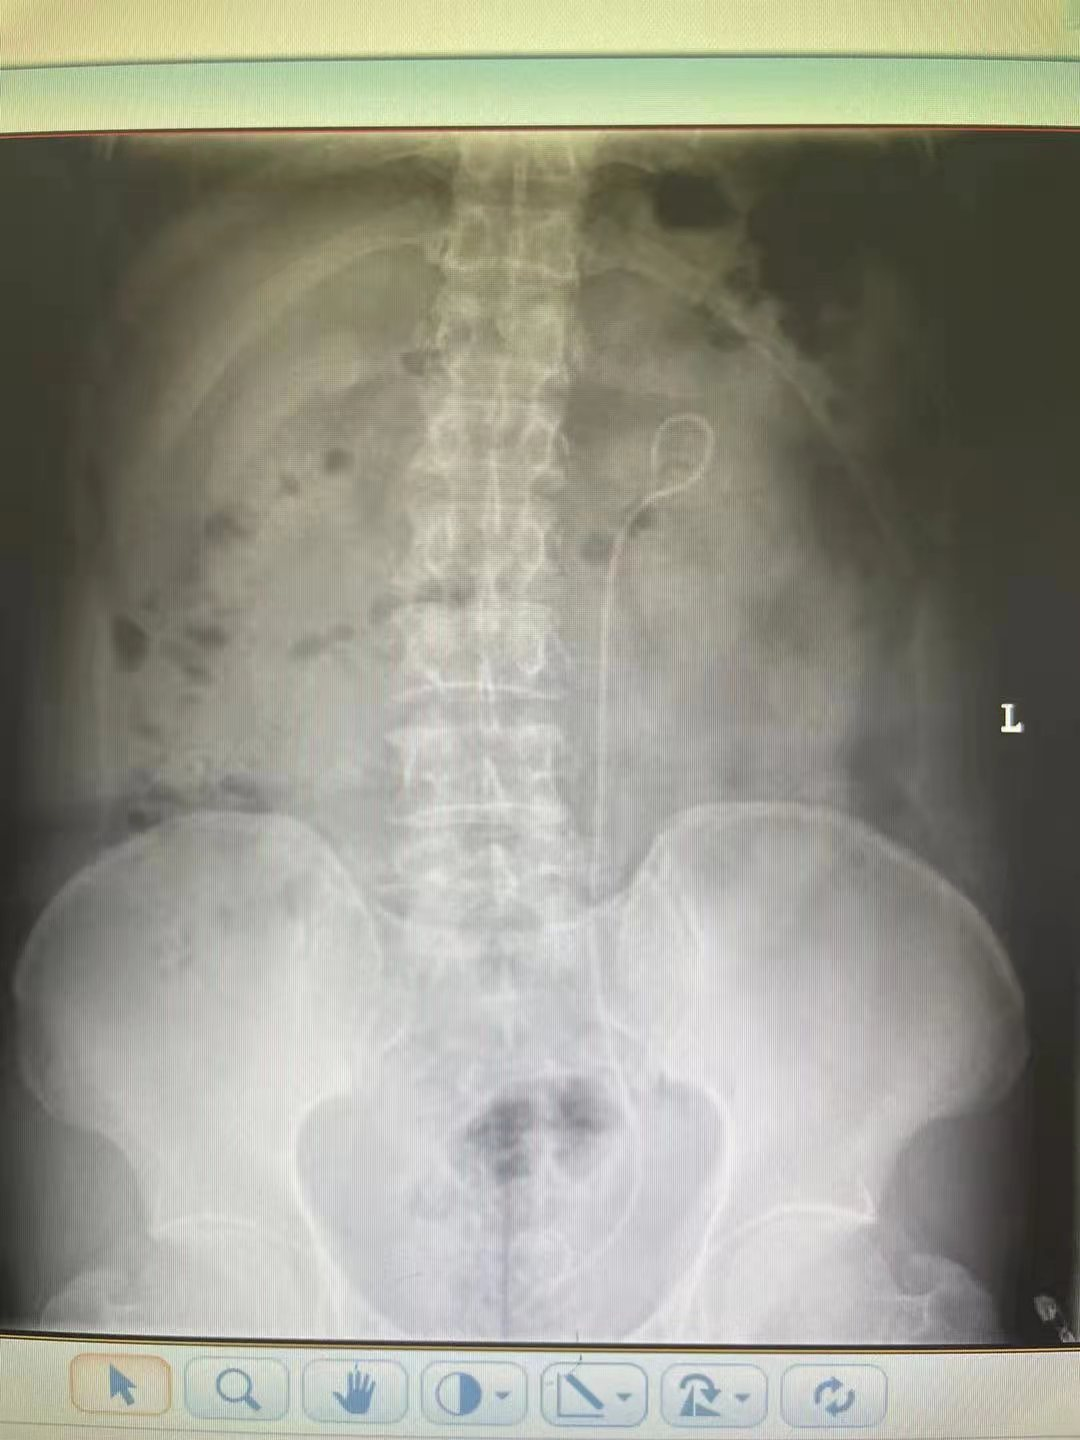

在家人的陪伴下,王先生來到太原市中心醫院急診做進一步檢查,行泌尿系CT檢查提示左側輸尿管中下段多發結石,血常規提示白細胞23.5X10^9/L,中性粒細胞95.4%,血壓90/60mmHg,心率115次/分。

入院后,泌尿科汾東病區專家考慮王先生輸尿管下段梗阻是導致感染性休克的主要原因。隨即,給予王先生抗感染、糾正休克治療。三天后,王先生的病情有所好轉,經研究討論,科室專家為王先生制定了安全周密的手術方案。